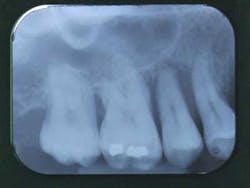

Fig. 1: Radiographic status of a 30-year-old Caucasian female

- Periodontal examination: The patient has very good oral hygiene, 6 mm to 9 mm pockets, bleeding on probing, and tooth mobility (especially tooth No. 4).

- Dental examination: Tooth No. 14 has been endodontically treated and now holds a PFM crown. Tooth No. 3 holds two tiny alloys.

- Functional examination: The patient reports no musculo-articular symptoms though lateral jaw movements exhibit working-side interferences on the premolars.

Diagnosis for this patient is an aggressive periodontal disease. The important periodontal bone loss is due to the combination of three risk factors:

Prognosis is poor for teeth Nos. 4, 12, and 15.

Fig. 2: Important bone loss around tooth No. 4